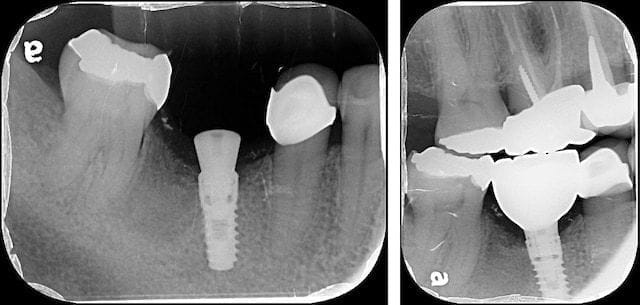

圖示:人工植牙手術修補缺牙。由左至右依序為:術前 / 置入人工牙根 / 植牙前補骨 / 鎖上癒合帽後縫合

因為植牙的穩定度還不錯,我們鎖上癒合帽後即縫合。這樣的條件我們大約等待兩個半月之後就可以開始製作假牙。

圖示:採人工植牙手術修補缺牙,左為人工牙根置入後,右為鎖上全瓷冠植牙假牙

我在植牙的假牙的材質幾乎都是使用全鋯冠(全瓷冠的一種,以二氧化鋯為材質製成),它的特色是一體成型且不易產生傳統假牙令人困擾的瓷裂問題。

設計是採用螺絲固位,這樣的好處是在未來比較容易再取下調整,同時避免在植牙常見因黏著劑不易徹底清理而引發植體周圍炎。